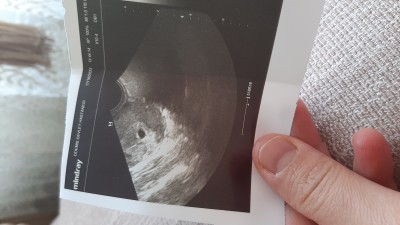

Adetin gecikmesi 2.gunu vajinal ultrasonda kese gozuktu 2 3 hafta sonra kalp atisi icin cagirdi kacinci haftada kalp atisi duydunuz siz

image